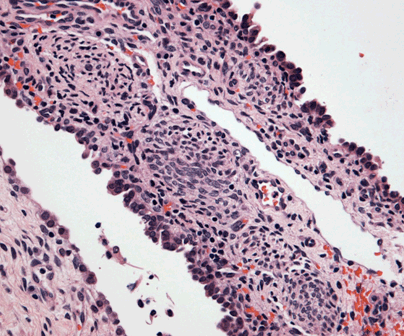

The histopathology examination showed hypercellular foci composed of primitive spindled and round cells.

![]() Figure 11 |

The above findings were consistent with the diagnosis of pleuropulmonary blastoma type I.